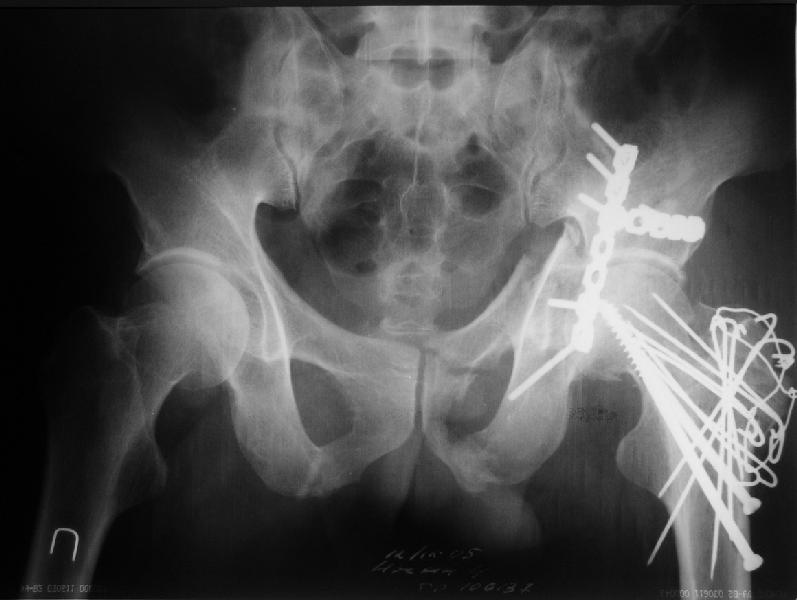

Уважаемые коллеги. Больной был оперирован в одну сессию 25 августа. Сначала на голень наложен спице-стержнвой аппарат. Затем выполнен остеосинтез вертлужной впадины Y-образным доступом. Пришлось дополнительно отсекать вертел. Шейка синтезирована спонгиозными винтами и спицами, вертел - спицами и стягивающей петлей. После операции находился на вытяжении 3 нед. Раны зажили первичным натяжением. Сейчас уже дома. Будет и дальше без нагрузки на левую ногу. Будем наблюдать в динамике. Ждем комментарии.